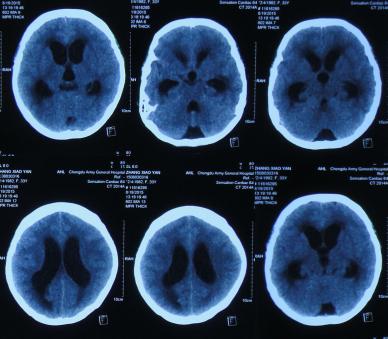

经头孢哌酮舒巴坦抗感染治疗1周后即2015年8月9日,仍间断头痛,发热有下降,但仍反复,但患者意识反变差,表情也变淡漠,查头部CT(图-2)。

图-2:2015年8月9日头部CT